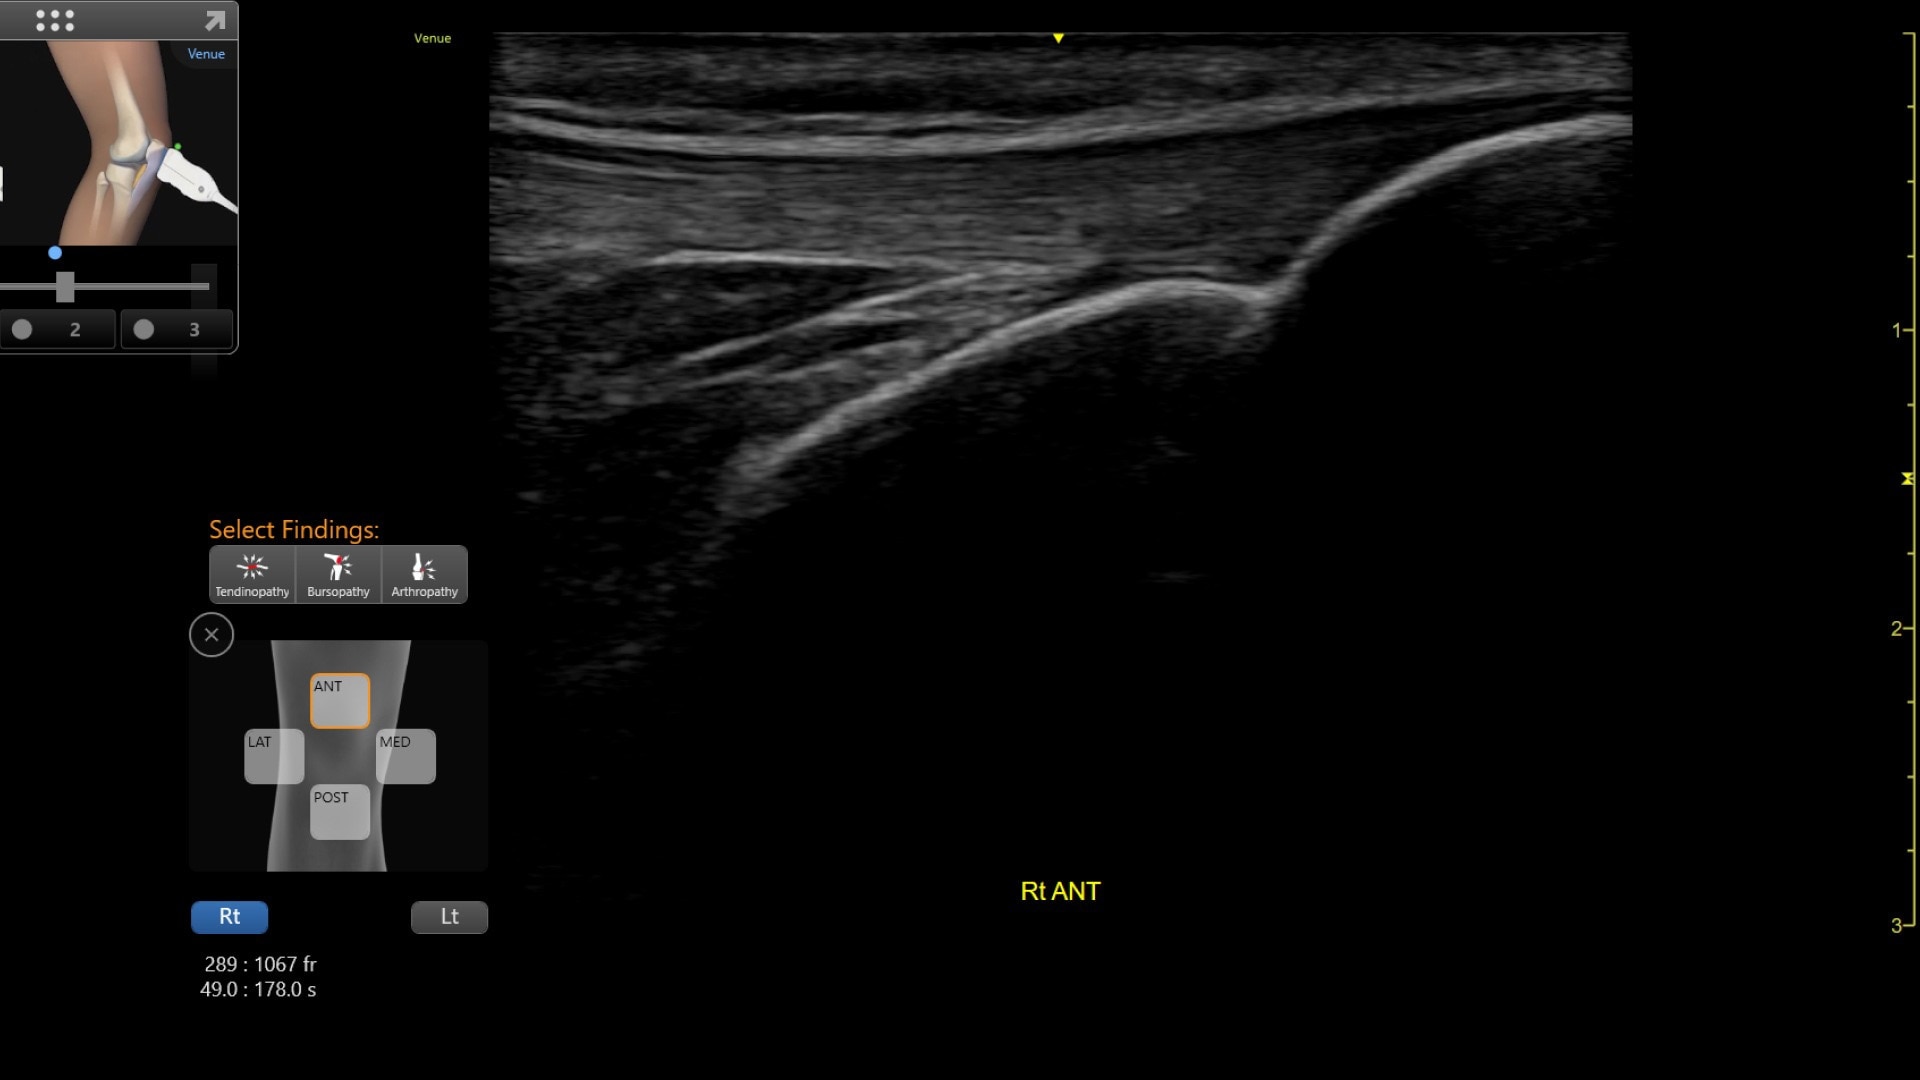

Precision Needle Guidance

Accurately guide and visualize injections

Even in the most experienced hands, blind injections—those performed without imaging—are not 100% accurate. By using ultrasound for needle guidance, the needle is highlighted and you have quality visualization of joints and soft tissue during procedures at a lower acquisition cost than other imaging modalities.

Excellent visualization with Needle Mode

Needle Mode also allows you to easily differentiate between the needle and patient anatomy with confidence—allowing you to quickly guide the needle exactly where it needs to be and helping to minimize patient discomfort.